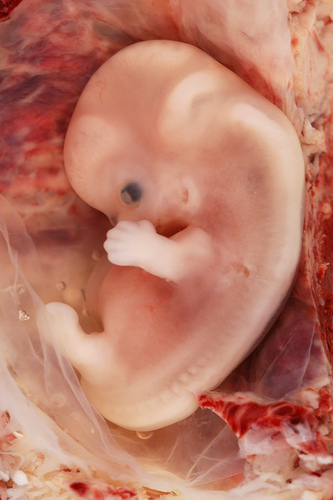

«Ἡ ἐπιστημονικὴ πρόοδος στὸν τομέα τῆς Ἐμβρυολογίας, ἀλλὰ καὶ ἡ τρισδιάστατη εἰκόνα τῶν ὑπερήχων πιστοποιοῦν τὴν ἀπὸ αἰῶνες διδασκαλία τῆς Ἐκκλησίας μας ὅτι ἡ ἀνθρώπινη ζωὴ ἀρχίζει «ἐξ ἄκρας συλλήψεως», δηλαδὴ τὴ στιγμὴ ποὺ τὰ 23 χρωμοσώματα τοῦ ὠαρίου ἑνώνονται μὲ τὰ 23 χρωμοσώματα τοῦ σπερματοζωαρίου καὶ δημιουργεῖται τὸ πρῶτο κύτταρο, τὸ ζυγωτό. Συγχρόνως, ὅμως, τότε σφραγίζεται καὶ ἡ προσωπικότητα τοῦ κάθε ἀνθρώπου, μὲ τὸ πλῆθος τῶν γονιδίων ποὺ παραλαμβάνει ἀπὸ τοὺς γονεῖς του.

Πρόσωπο μοναδικὸ καὶ ἀνεπανάληπτο θεωρεῖται τὸ ἔμβρυο καὶ ὡς τέτοιο ἀναγνωρίζεται παγκοσμίως. Ὡς «πρόσωπο» τὸ ἀναγνωρίζει καὶ τὸ Δίκαιο τῆς πατρίδας μας καὶ τὸ καθιστᾶ ὑποκείμενο καὶ φορέα ἀστικῶν δικαιωμάτων, π.χ. τὸ ἄρθρο 1711 τοῦ Ἀστικοῦ Κώδικα, σύμφωνα μὲ τὸ ὁποῖο τὸ συλληφθὲν ἔμβρυο μπορεῖ νὰ κληρονομήσει περιουσιακὰ στοιχεῖα συγγενῶν του, ἐὰν γεννηθεῖ ζωντανό.